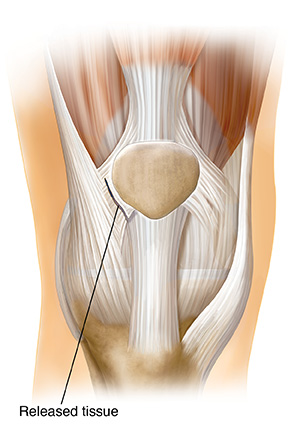

Releasing tissue (lateral release)

This is done with either open surgery or arthroscopy. Releasing (cutting) the retinaculum reduces the pull on the kneecap so that it moves into its correct place. The retinaculum is a band of tissue on both the inside and the outside of the kneecap that assists its motion. Releasing a plica band may also reduce pain. Plica bands are thick, fibrotic bands that may be found in several areas inside the knee joint.